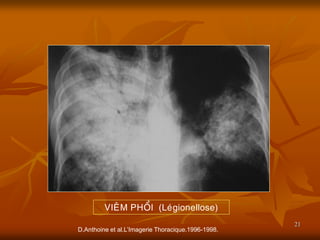

D.Anthoine et al.L’Imagerie Thoracique.1996-1998.

VIEÂM PHOÅI (Leùgionellose)